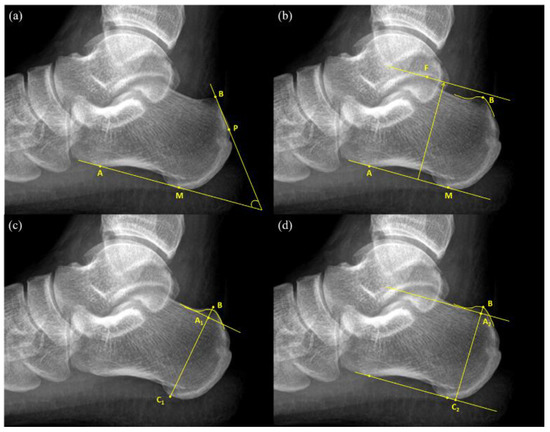

An FPA is the angle between the tangent line to the rear edge of the greater tuberosity of the calcaneal and the line connecting the anterior tubercle and medial tuberosity of the calcaneal (Figure 1a). The normal values of FPA range from 44° to 69°, and values greater than 75° are considered indicators of pathological changes [9].

Heneghan–Pavlov PPL is the baseline formed by the line connecting the anterior tubercle and medial tuberosity of the calcaneus and a parallel superior line passing through the superior aspect of the talar articulation (Figure 1b). If PPL passes through the prominence of the posterosuperior edge of the calcaneal tuberosity, it is considered positive [10].

Haglund’s deformity height ( BA 1 ¯ ) (Figure 1c) was obtained first by drawing a reference line at the base of the posterosuperior calcaneal prominence and then by measuring the vertical distance between the vertex of the bump and the reference line [13]. Next, calcaneal height ( BC 1 ¯ ) was measured as the vertical distance between the vertex of the bump and the reference line drawn tangent to the lower edge of the calcaneus. Haglund’s height ratio was calculated as the ratio of Haglund’s deformity height to calcaneal height ( BA 1 ¯ / BC 1 ¯ ) (Figure 1c).

This study put forward two novel measurement methods for the diagnosis of Haglund’s deformity, namely bump height and bump-calcaneus ratio. Firstly, the baseline tangent to the anterior tubercle and medial tuberosity of the calcaneus was drawn. The baseline was moved upward parallelly until it touched the superior edge of the calcaneus, which was considered the reference line for bump height different to that in Haglund’s deformity height. Then, the reference line was moved upward parallelly again until it reached the superior edge of the bump and the intersection point was considered as the vertex of the bump (point B). The vertical distance between the vertex of the bump and the reference line was measured as bump height ( BA 2 ¯ ), whereas the vertical distance between the vertex of the bump and the baseline was measured as calcaneal thickness ( BC 2 ¯ ). Then, bump-calcaneus ratio was calculated by dividing bump height ( BA 2 ¯ ) by calcaneal thickness ( BC 2 ¯ ) (Figure 1d).

Figure 1. Radiographic measurement of Haglund’s deformity (a) Fowler-Philip angle = Angle between AM   ¯ and BP   ¯ ; (b) Heneghan-Pavlov parallel pitch lines; (c) Haglund’s height = BA 1 ¯ ; Haglund’s height ratio = BA 1 ¯ / BC 1 ¯ ; (d) Bump height = BA 2 ¯ ; bump-calcaneus ratio = BA 2 ¯ / BC 2 ¯ .